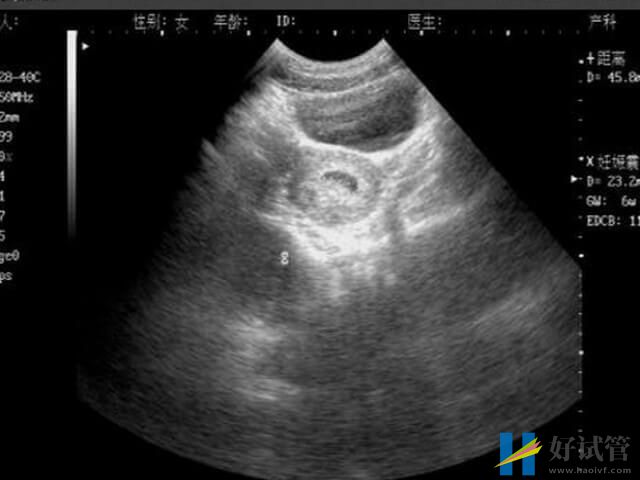

为什么孕9到11周最容易发生胎停?

并非只是在孕9到11周最容易发生胎停,而是在怀孕早期的任何时间内胎停发生概率都是非常之大的,毕竟在怀孕早期的时候,胚胎发育不完善、胚胎着床不稳定以及胎盘没形成等因素都是会导致胎儿停止发育即胎停育的。一般来说,此时间内发生胎停的概率在10%-20%左右,但是具体的胎停率是因人而异的,毕竟每位女性之间都存在个体差异,而且胚胎的质量也存在着个体差异。

胎停在临床中称为胚胎停育,是指由于某种原因导致的胚胎停止发育,可进一步引起胚胎死亡。一般来说,胎停的发生概率最好的阶段就是怀孕早期的时候,其原因大致就如下所列: